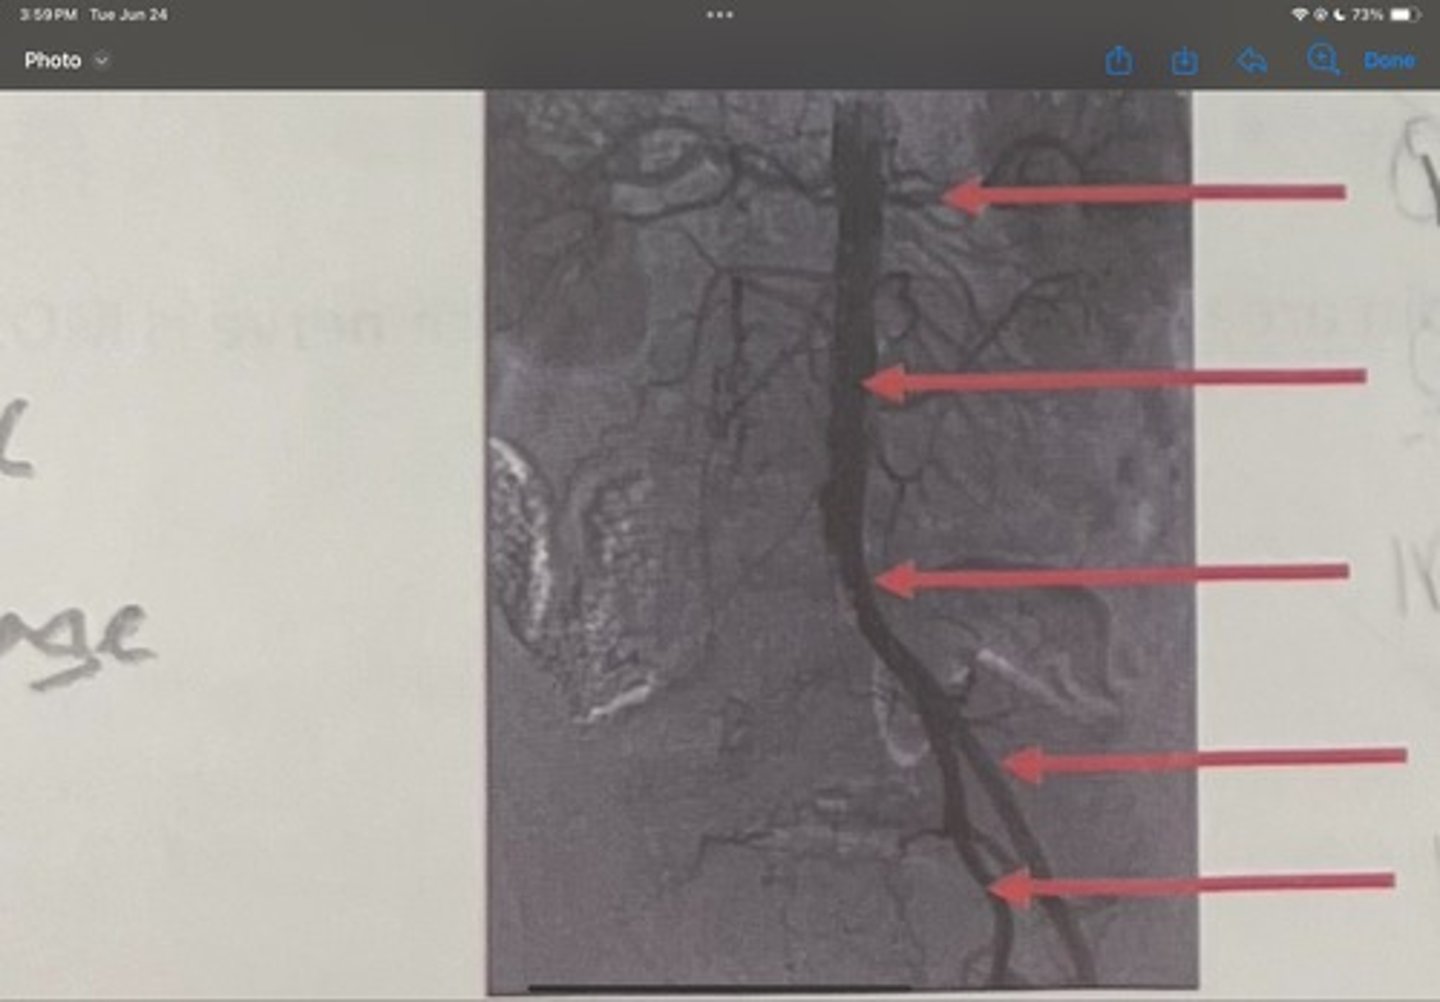

Renal artery

What is the 1st one

Abdominal aorta

What is the 2nd one

Common iliac artery

What is the 3rd one

External iliac artery

What is the 4th one

Internal iliac artery

What is the 5th one

right common iliac artery blockage

What is the pathology of the image